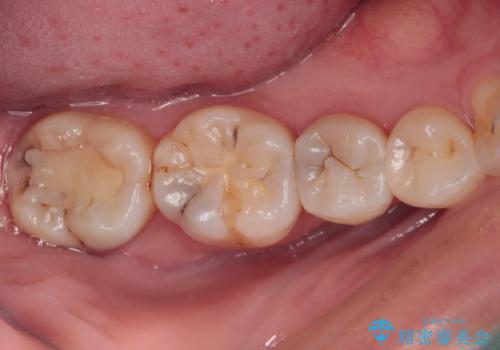

- 奥歯に頻繁に物が挟まるとのことで来院された患者様です。

最近ものが挟まりやすくなったり、冷たいものがしみるようになったりといった症状があり、診査したところ、むし歯や歯質の欠損、不適修復物などが認められました。

精度の高いセラミックインレーによる修復治療を行うこととしました。